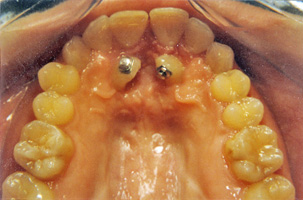

Υπερκάλυψη των κάτω προσθίων δοντιών, συνωστισμός, έγκλειστοι κυνόδοντες στην άνω γνάθο κι έκτοποι κυνόδοντες στην κάτω γνάθο. Ορθοδοντική θεραπεία σε συνδυασμό με γναθοχειρουργική αποκάλυψη των άνω κυνοδόντων.

Πριν τη Θεραπεία